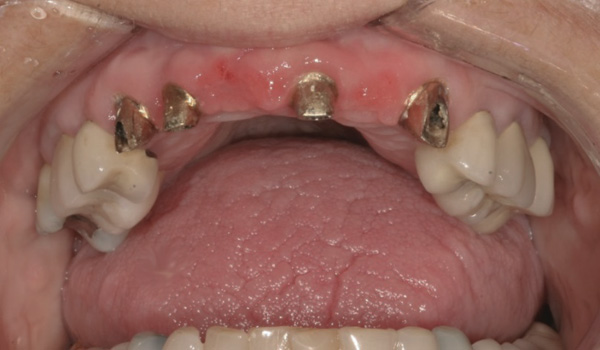

Background: This patient presented with a failing maxillary bridge spanning teeth Nos. 6 through 11. In order to keep the patient in a fixed transitional prosthesis, the first phase of treatment involved placing a provisional restoration on Nos. 6 through 11, with the first set of implants placed at sites Nos. 6 and 11. Once implants Nos. 6 and 11 integrated, custom abutments were placed, and the provisional was relined to add their support. Then implants and their respective subsequent abutments could be placed at positions Nos. 7 and 9 (Figure 20). Tooth No. 8 received elective endodontic treatment in order to be reduced and eventually submerged following insertion of the abutments at Nos. 7 and 9 (Figure 21 and Figure 22).

Results: In Figure 22, it is apparent that there is no recession around abutments Nos. 7 and 9 following root submergence. Of additional note, Figure 23 illustrates excellent bone labial to all the implants, with no recession around abutments Nos. 6 or 11. These first abutments were inserted 8 months prior to the ones at Nos. 7 and 9. The time between Figure 21, when root submergence took place, and Figure 23, when the final bridge was to be inserted, was 7 months. Figure 24 shows placement of the provisional bridge on all abutments.

Figure 20 Implants and their respective subsequent abutments placed at Nos. 7 and 9.

Figure 20

Figure 21 Endodontically treated tooth No. 8.

Figure 21

Figure 22 Tooth No. 8 eventually submerged following abutment insertion at Nos. 7 and 9.

Figure 22

Figure 23 Excellent bone labial to all the implants; no recession around abutments Nos. 6 or 11.

Figure 23

Figure 24 Provisional bridge on all abutments.

Figure 24